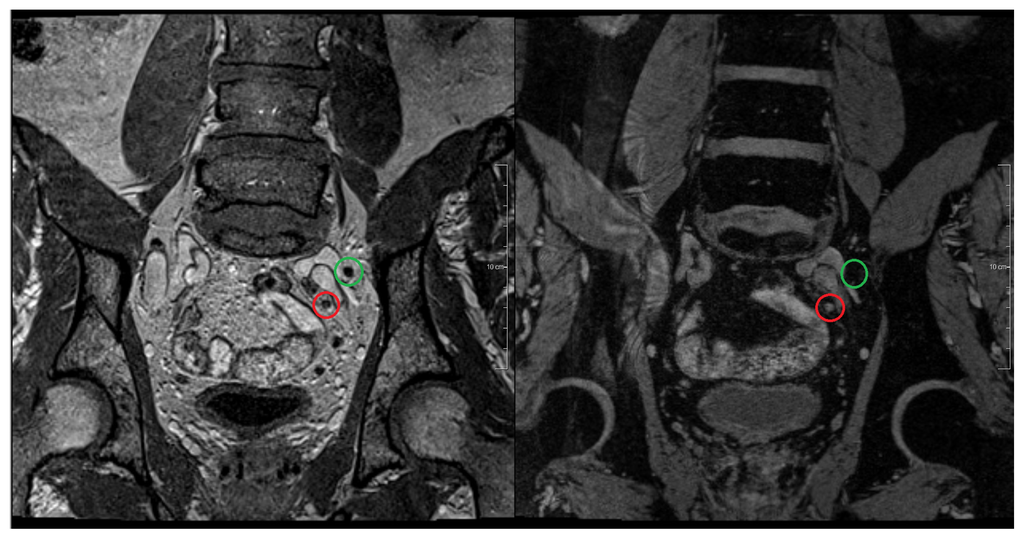

Figure 3.

MR-lymphography at 3 Tesla using USPIO. Patient with prostate cancer and lymphatic metastases. Left image shows the morphological T1 weighted coronal sequence with two small lymph nodes near to the left common iliac artery. Right image shows the corresponding T2* weighted coronal image 24 h after the intravenous administration of an USPIO agent (ferumoxtran-10). The lymph node marked by the green circle shows an USPIO uptake and therefore a signal loss in the T2* image suggesting normal lymphatic tissue. The lymph node marked by the red circle does not show any USPIO uptake and therefore shows a bright signal on the T2* image. This lymph node is highly suspect for metastasis.